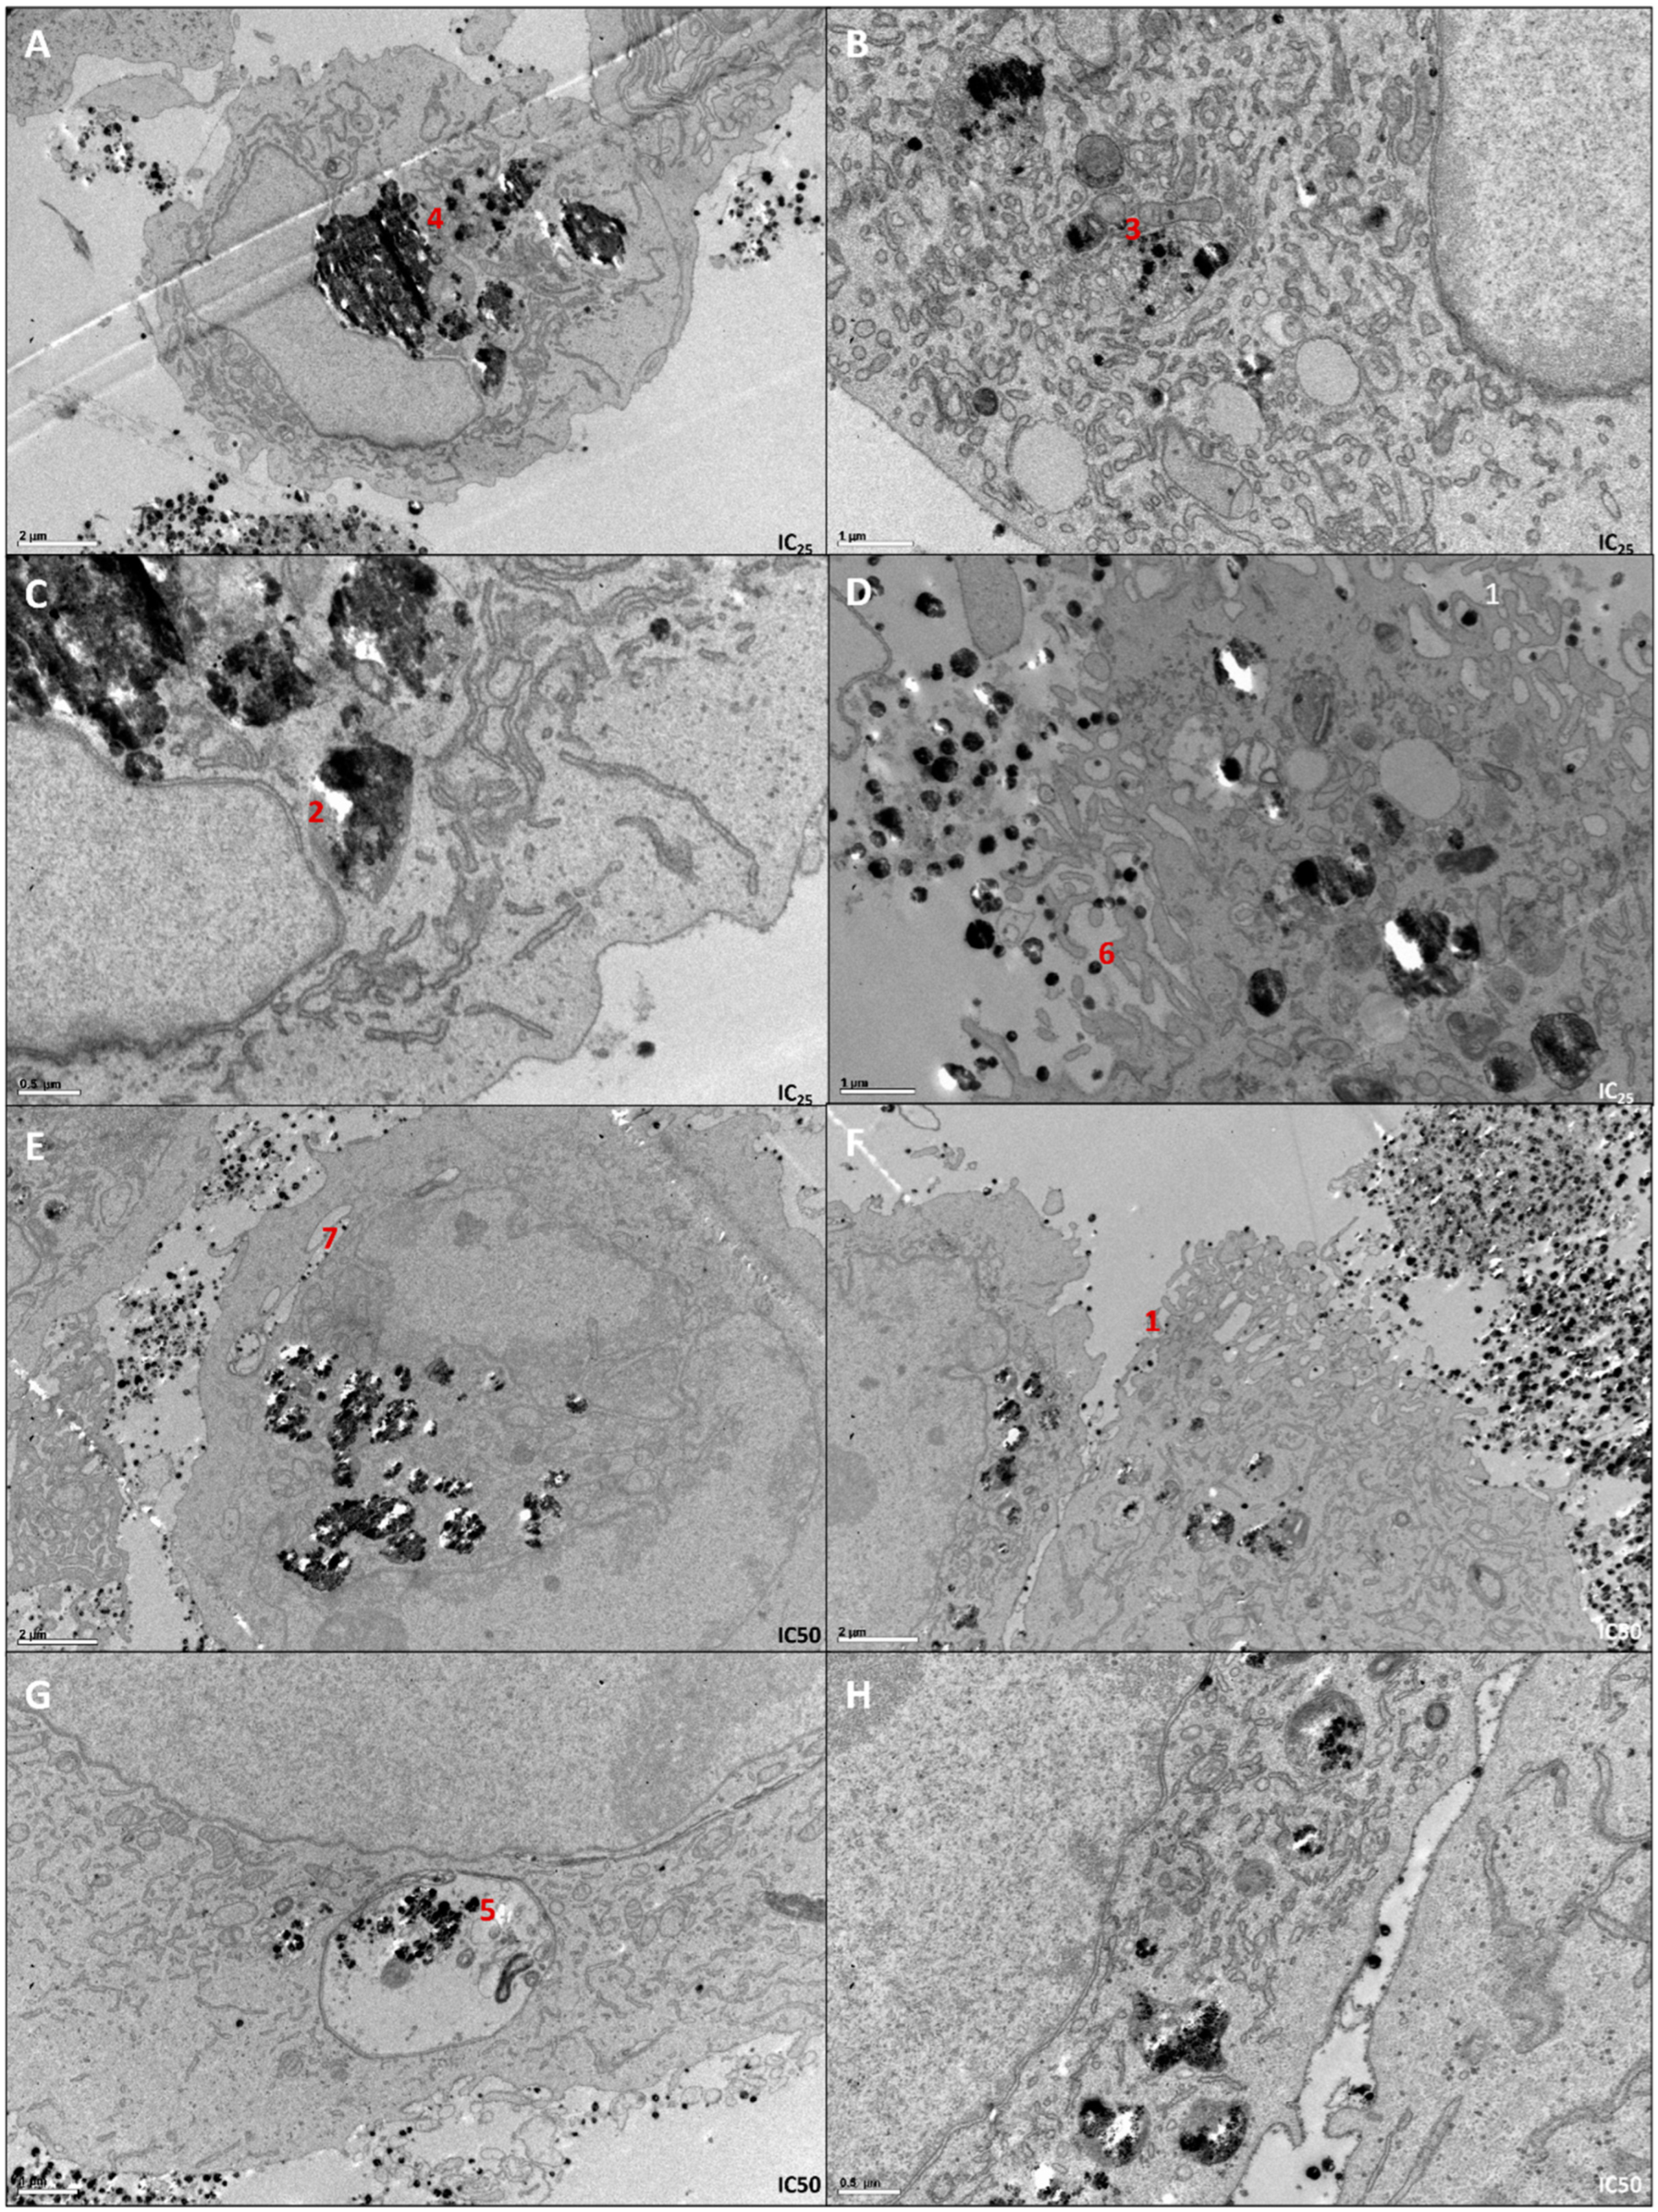

Using these two concentrations, a TEM analysis was performed in order to evaluate the internalization process and AgNPs’ location inside the cell (Figure 2). Through TEM analysis, it is possible to observe that cells seem to form invaginations to internalize the AgNPs (Figure 2F1). Inside the cell, AgNPs are located near the nucleus (Figure 2C2), mitochondria (Figure 2B3) and the Golgi complex (Figure 2A4), being integrated inside vacuoles resembling lysosomes (Figure 2G5). It is important to notice that cells display apoptotic features (Figure 2D6) and AgNPs keep their monodisperse nature inside the cell (Figure 2E7).

Figure 2. TEM images of 786-O cells treated with IC25 (AD) and IC50 (EH) of AgNPs. From each sample, pictures were taken with different ampliations. Thus, scale bars in (A,E,F) are 2 µm, in (B,D,G) are 1 µm and in (C,H) are 0.5 µm. 1—Cell invaginations capturing AgNPs; 2—Nanoparticles localized near the nucleus; 3—Nanoparticles localized near mitochondria; 4—Nanoparticles localized near Golgi complex; 5—Nanoparticles trapped inside lysosomes; 6—Apoptotic features of 786-O cells; 7—Nanoparticles monodisperse nature.

In the present study, we observed a dose-dependent cytotoxic effect in the 786-O cell line but not in RCC-FG2 and Caki-1. It is known that AgNPs show heterogeneous effects according to the cell line, with their effect being cell type-specific, and the lower effect in these cells may be explained by their more aggressive phenotype [18]. Interestingly, the mechanism of action in 786-O is consistent with what our group previously observed [10]. This mechanism is common to many studies with other AgNPs where authors report an increase in ROS production, mitochondrial damage, nuclear fragmentation and cell apoptosis [9]. In this case, as shown by TEM analysis, AgNPs enter cells through endocytosis and are trapped in lysosomes, which have hydrolytic enzymes that can decompose the capping and release Ag+ [19]. These ions will induce the production of ROS, increasing oxidative damage in the different organelles. Interestingly, in the present study, the increase in ROS induced by AgNPs was even higher than the signal induced by t-bhp (the positive control of the experiment), suggesting that ROS production is indeed a key player in AgNP’s toxicity. In this study, we observed significant damage in mitochondria and a blockage of the cell cycle in the S phase. The S Phase checkpoint is responsible for DNA damage check, which can indicate that AgNPs also induce damage in the nucleus, supporting the cell arrest observed in the present study [20]. Moreover, this damage is enough to trigger apoptosis, as observed with FITC annexin V and PI staining. Additionally, the results obtained through the FITC annexin V and PI staining assay, strengthen the results observed through resazurin assay, since they can be a marker of the percentage of viable cells in opposition to the ones in apoptosis and necrosis.